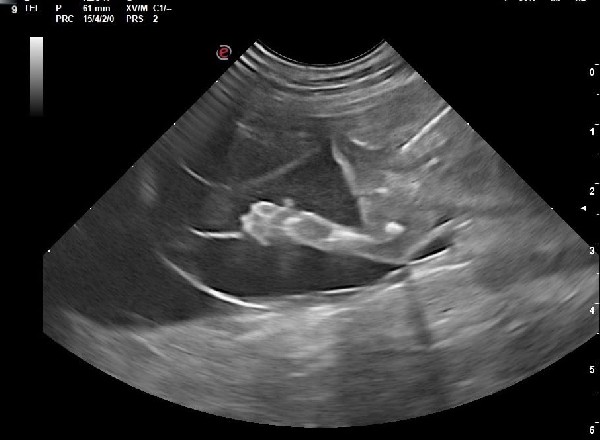

En plus de confirmer la gestation, elle permet de contrôler l’aspect des ampoules, des placentas, des ovaires et de l’utérus. Elle permet aussi d’estimer avec une bonne précision le nombre de chiots si elle est faite au moment optimal (autour de J25 post-ovulation). Si la date d’ovulation n’est pas connue, l’échographie peut permettre de dater la gestation grâce à différentes mesures anatomiques et à l’évolution des structures anatomiques visibles à l’échographie. Elle permet également de mettre en évidence et de suivre d’éventuelles résorptions embryonnaires et nous amène alors à réaliser d’autres examens.

Dans certains cas de figure, notamment lors d'antécédents d'avortement, un suivi de la progestéronémie peut être recommandé au cours de la gestation et peut être associé à des contrôles échographiques.